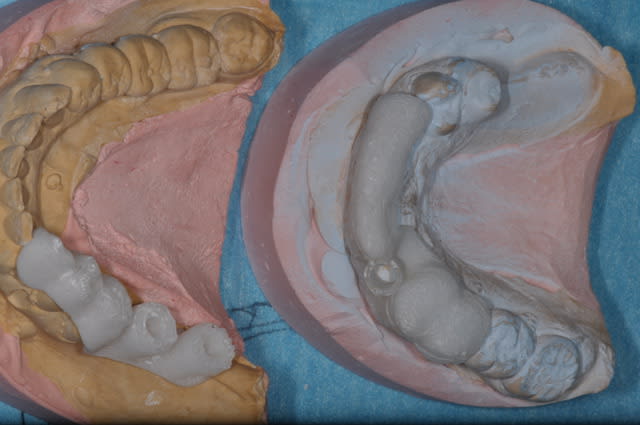

Here an imaginary case where prosthetic plan drives implant placement and a temporary bridge shell could be made to pick up temporary abutments....

Final case p1celi - Eugenol